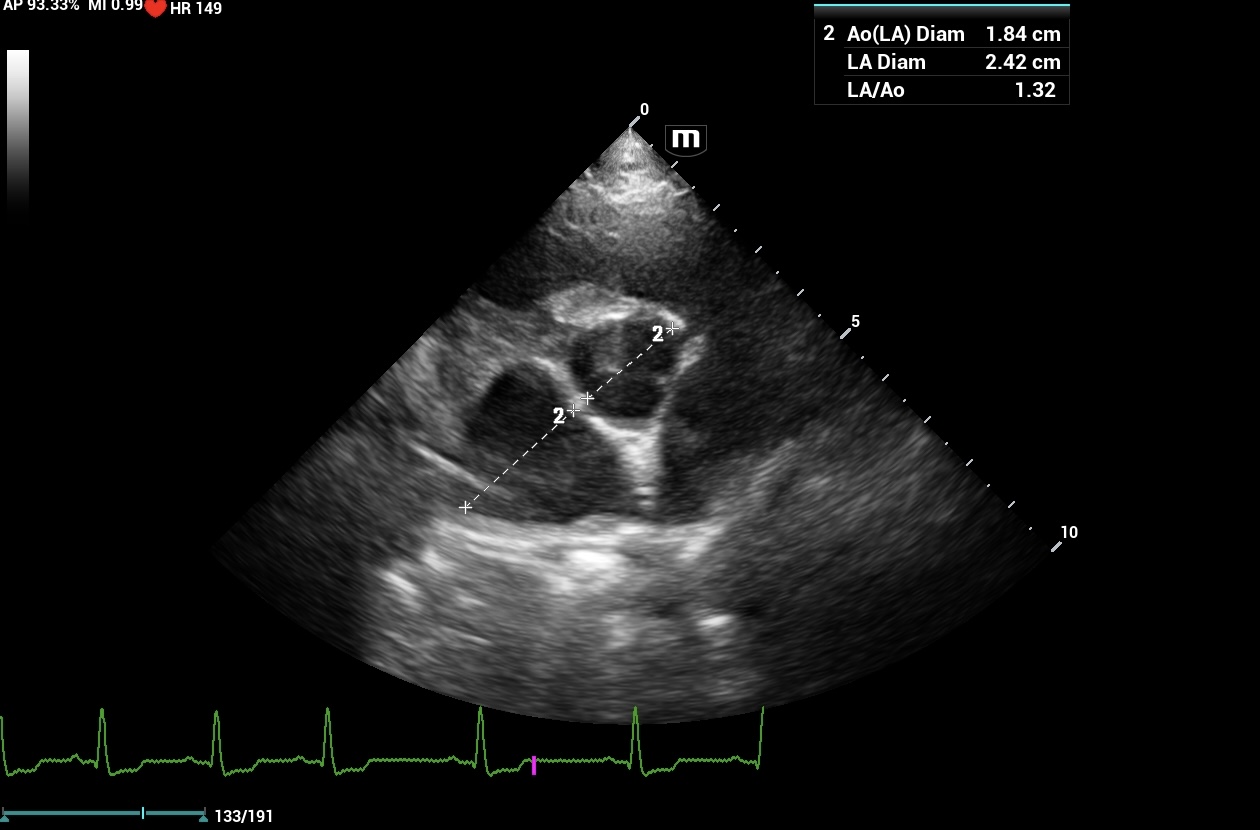

14Kg KCCS Dog; 3/6 murmur placed on Pimo after rads. Echo(3 wks later) revealed mild mod MV reg, TV reg and AO ins. PG – MV and TV=N. AO PG=N with plateau flow profile. Echo = stage B1 MVD, BP= N.Dog was 5 lbs ovweight. C index adj. to 11.7Kg= N.

Sonographically B1 and B2 I go to the atrial septum and ensure its deviated toward the right atrium and not in line wiht the IVS. Your echo the AS is in line wiht the UVS and not deviated and there fore no LAE in this case. I use the LA max measurement and ensure there is a solid MR jet and not a small one. I dont have rads available in many of my interps so from the sonographer perspective this tends to work well. If pimo other tx has been given and the LA is normal and you dont know if the LA is normal because of tx or its normal because it didnt need it, then I go to the level of MR because the MR has to have. alarge regurguitant flow to eventually cause LA enlargement. Then of course checking rads to see if they misinterpreted the rads as LAE which happens a lot. Otherwise stop the pimo for a week and rescan and see what the lA is doing. If just B2 they should be good wihtout tx for a week to find out if the tx direction is correct. Your case looks very B1. Hope this helps

No LAE on rad, VLAS =1.74,VHS = high normal for a KCCS 11.78. Echo was normal. The heart had a few minor “leaks” , dog was being treated and the owner felt the dogs activity and energy improved on meds. Wasn’t sure if increased quality noted in a B1 dog put on meds would warrant continuation or one should always follow protocol. It’s possible owner subjectivity could be biased too.Will stop meds and observe response.